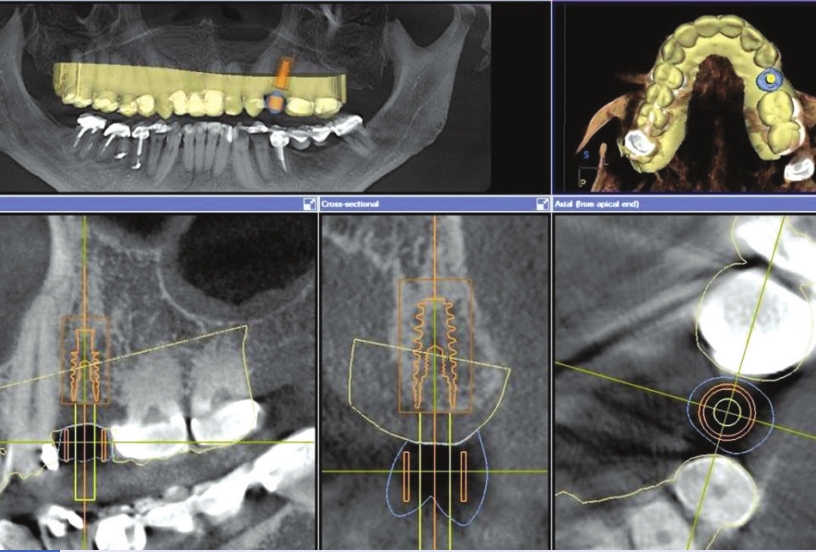

Then

the two scans are stitched together (virtually overlapped) to plan a

dental implant in the ideal position to support the future tooth already

designed. By stitching both images, one can see where the details of

the future crown lie and planning of the implant position is able to be

done confidently. This “perfect placement” assures we have the proper

loading forces (compression from chewing) on our future crown for the

implant and supporting bone structure. Here, we can also determine if an

extra bone augmentation procedure is necessary.